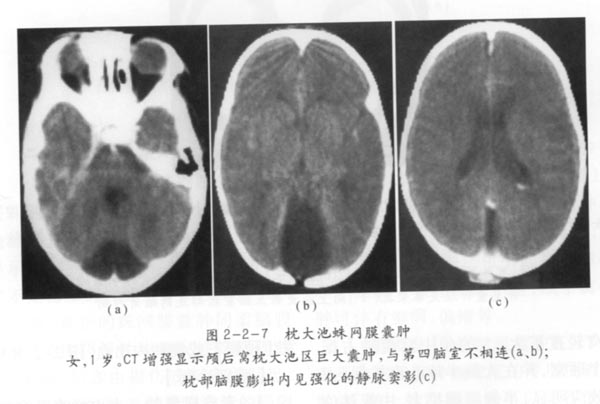

枕大池蛛网膜囊肿02

抄自《儿童ct诊断学》 朱杰明 主编 上海科学技术出版社 2003年10月第1版